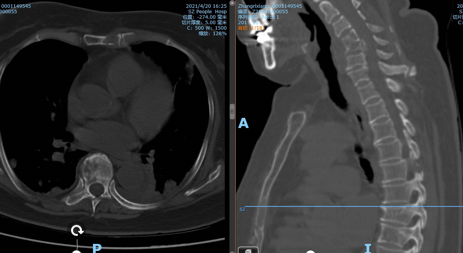

此为阿姨术后的X光,明亮处为骨水泥

此为张阿姨手术后的CT图像,可以看见张阿姨的椎体被骨水泥填充的同时,也进行了内固定处理,这样做不仅缓解了疼痛、破坏了肿瘤细胞,同时也对颈椎起到了强有力的固定。保持其稳定性。